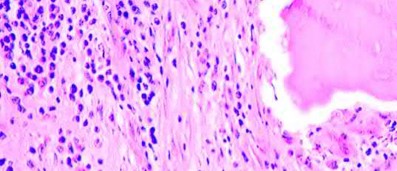

A 35-year-old female presents with a lytic lesion in the distal femur. Biopsy confirms Giant Cell Tumor (GCT) of bone.

Due to the proximity to the joint and tumor size, the multidisciplinary tumor board recommends neoadjuvant treatment with denosumab prior to curettage. What is the specific molecular mechanism of action of denosumab in treating GCT?

Explanation

Giant Cell Tumor of bone consists of neoplastic mononuclear cells that express high levels of RANK Ligand (RANKL), which recruits and activates reactive multi-nucleated osteoclast-like giant cells that cause the extensive bone destruction. Denosumab is a fully human monoclonal antibody that binds directly to RANKL. By neutralizing RANKL, denosumab prevents the interaction with the RANK receptor on the surface of osteoclast precursors and giant cells, thereby profoundly inhibiting osteolysis and allowing the tumor bed to ossify.